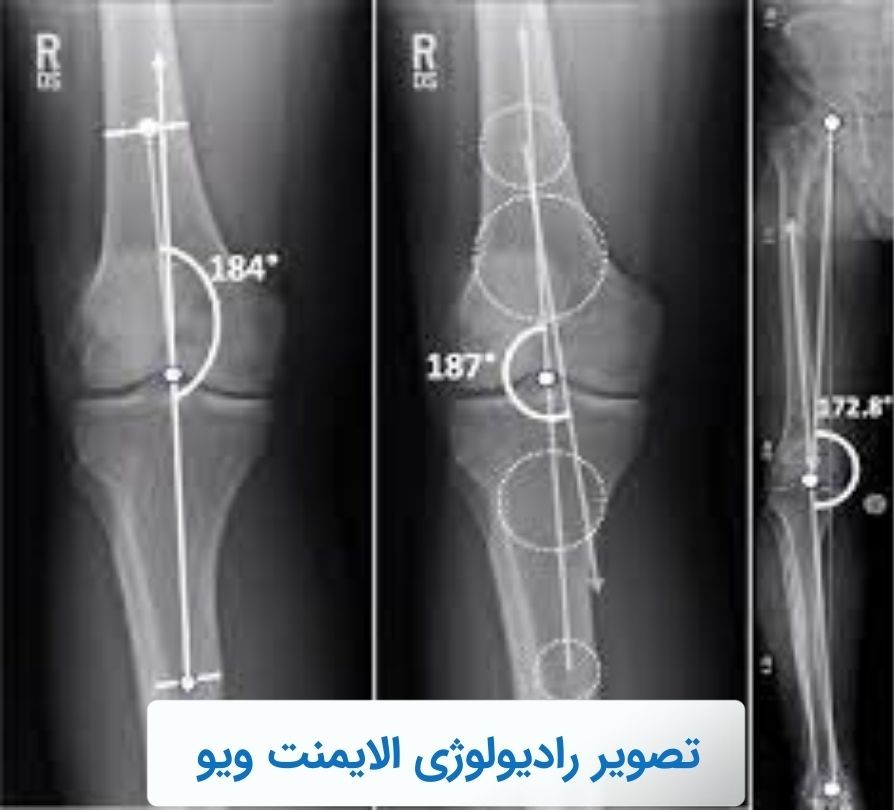

بدشکلی و غیرهمتراز بودن اندامهای تحتانی، بهخصوص پاها، در علم پزشکی با عنوان انحراف از محورهای فيزيولوژيکی تعريف ميشود. این مشکل ممکن است یک علت مادرزادی یا ساختاری داشته باشد. تصویربرداری سی تی اسکن و ام آر آی میتوانند اطلاعات دقیقی در این زمینه ارائه دهند. اما معمولا در مرحله اول پزشکان به سراغ رادیولوژی الایمنت ویو (Alignment view) میروند. چراکه میتواند بخشهای مختلف پاها (لگن، مچ پاها و زانوها) را در قالب یک عکس نشان دهد و به پزشک کمک کند تا انواع مشکل به ویژه انحراف پاها را تشخیص دهد.

رادیولوژیست میتواند این تراز را با کمک رادیولوژی الایمنت، از مرکز لگن تا مرکز مچ پا ترسیم کند و هرگونه بدشکلی را گزارش دهد. البته رادیوگرافی الایمنت برای بررسی طول ستون فقرات و ارزیابی انحراف احتمالی آن نیز گزینه مطلوبی است.

معمولا پزشک برای تشخیص نهایی و اطمینان از انحراف در راستای طبیعی اندامها، در مرحله بعد دستور انجام رادیولوژی الایمنت ویو را میدهد. این آزمایش تصویربرداری برای ارزیابی نوع و شدت اختلال انحراف پاسخگو است.